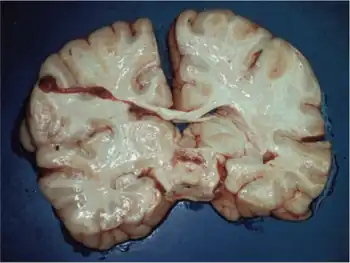

Pathophysiology

The characteristic symptoms of Leigh syndrome are at least partially caused by bilateral, focal lesions in the brainstem, basal ganglia, cerebellum, and other regions of the brain. The lesions take on different forms, including areas of demyelination, spongiosis, gliosis, necrosis, and capillary proliferation.[7]

Demyelination is the loss of the myelin sheath around the axons of neurons, inhibiting their ability to communicate with other neurons. The brain stem is involved in maintaining basic life functions such as breathing, swallowing, and circulation; the basal ganglia and cerebellum control movement and balance. Damage to these areas therefore results in the major symptoms of Leigh syndrome—loss of control over functions controlled by these areas.[1]